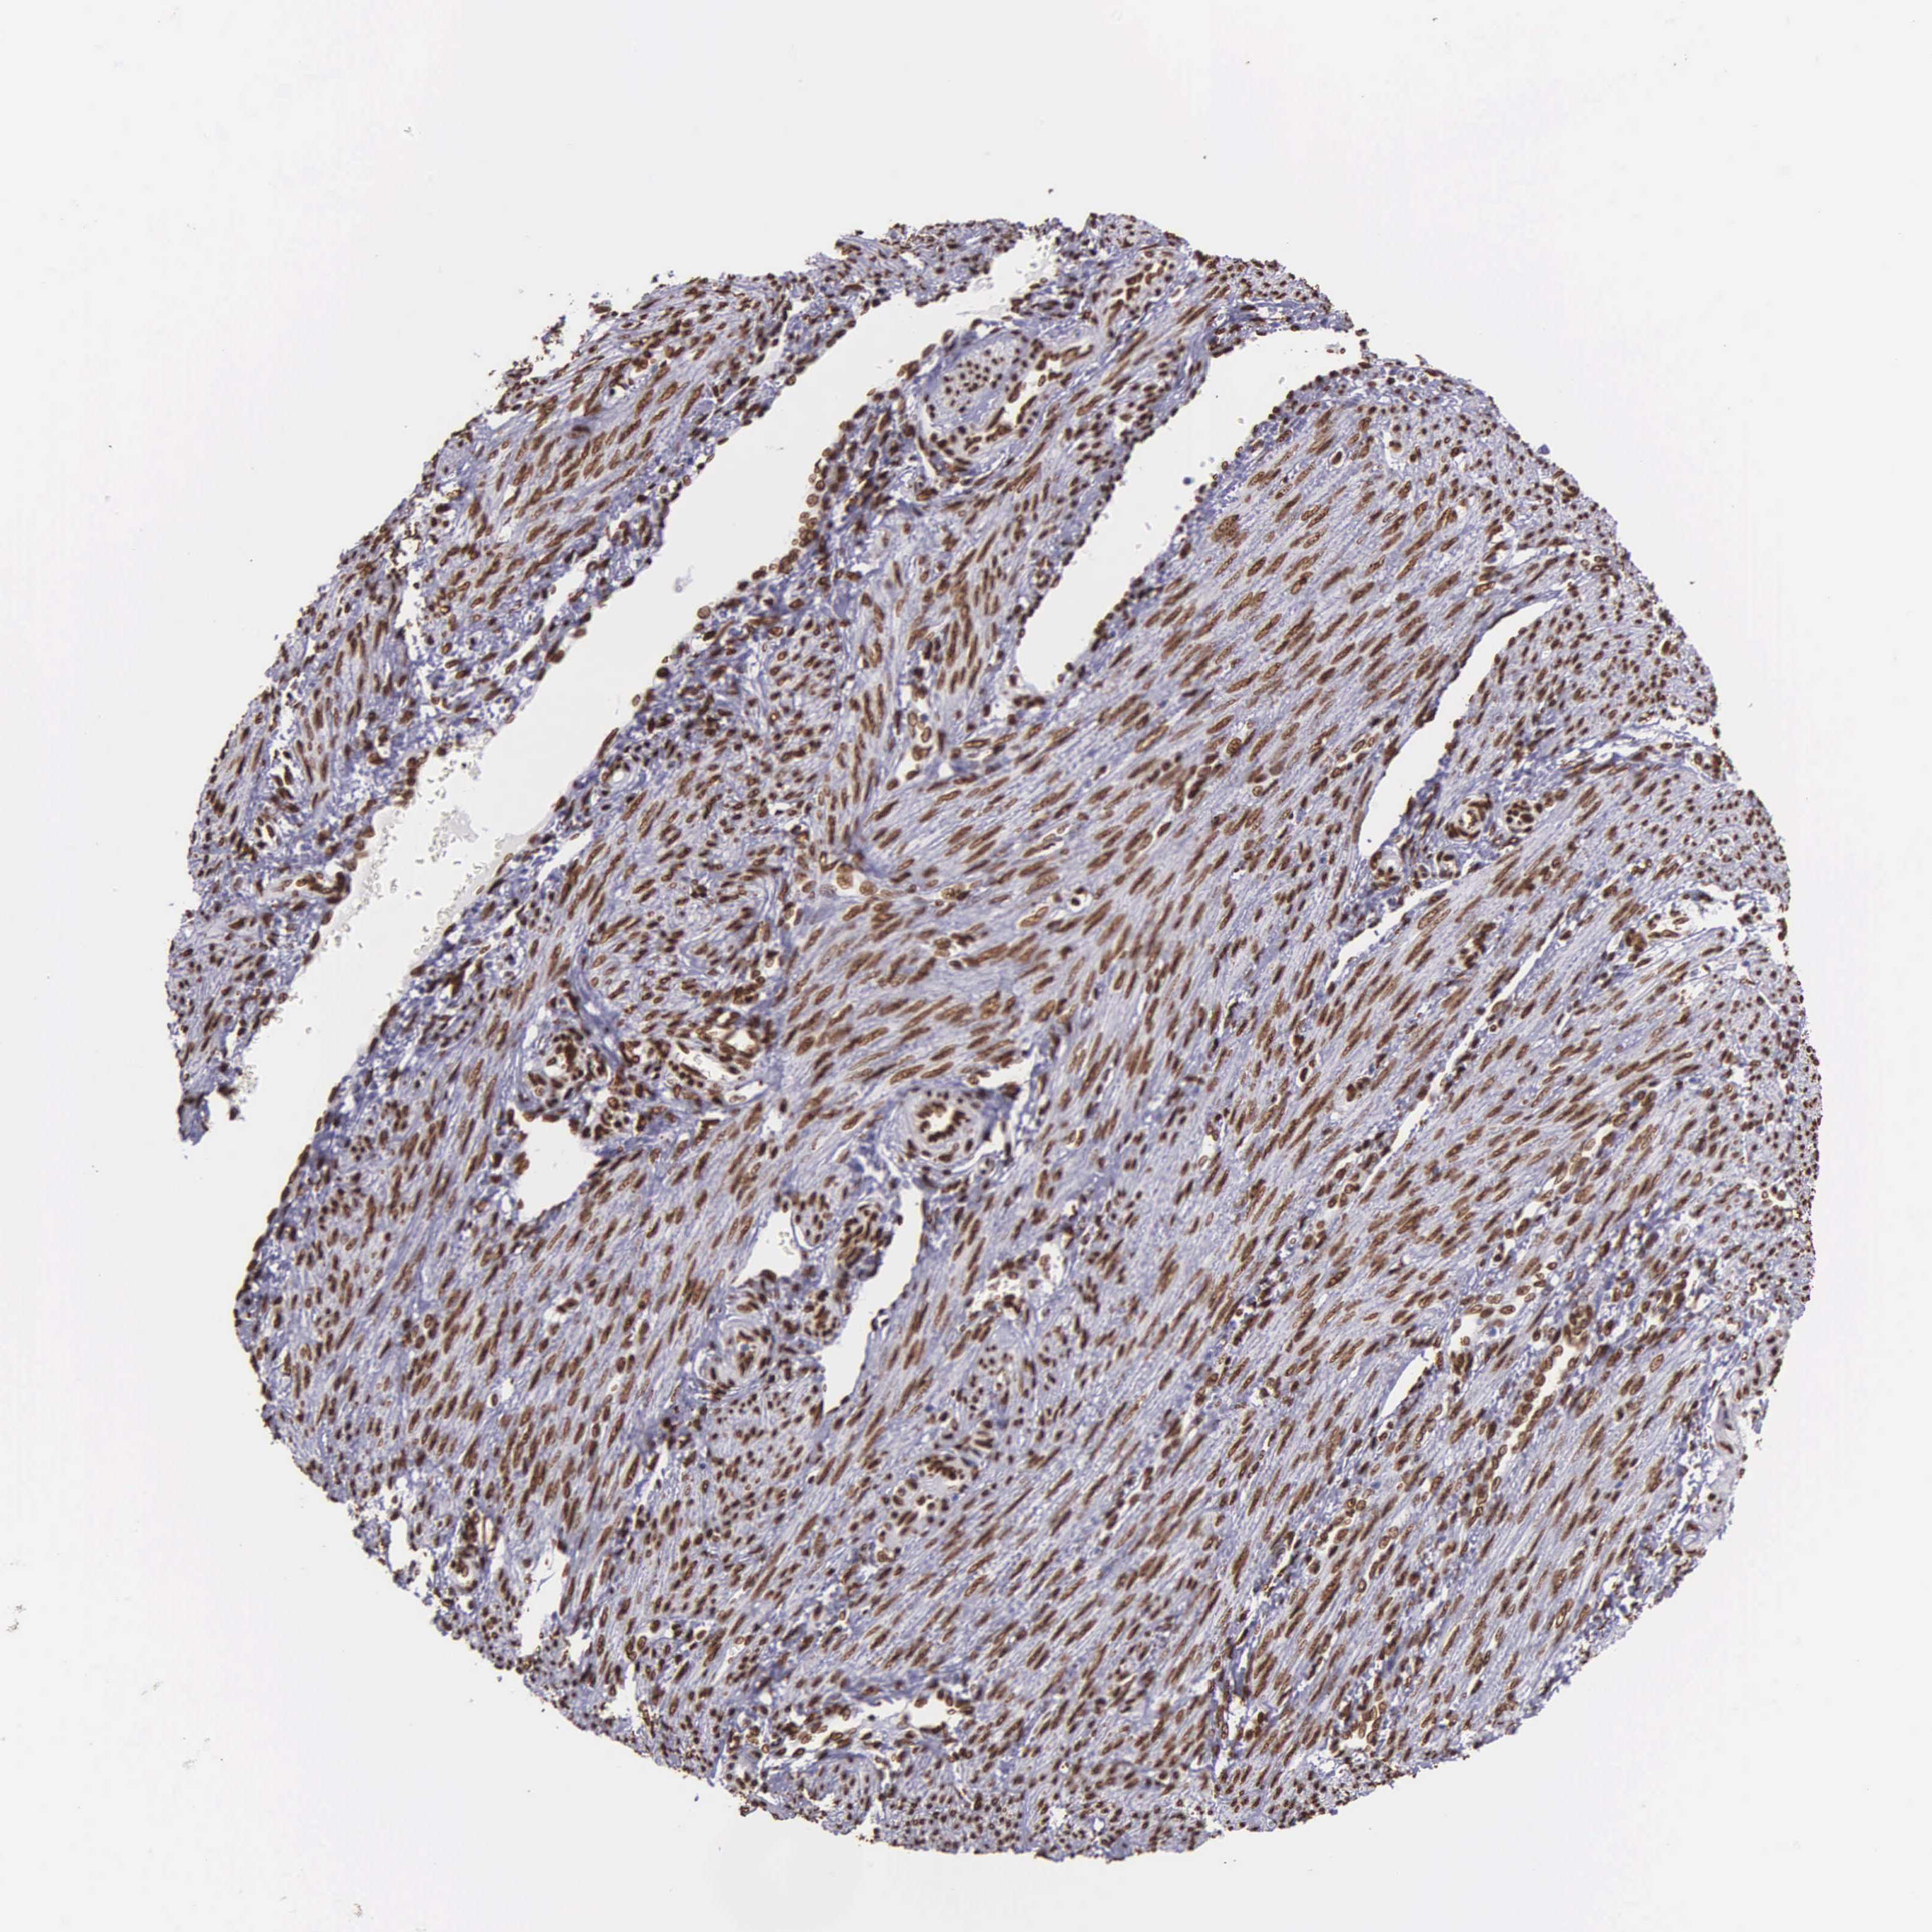

ENDOMETRIAL CANCER - Protein expressioni

A mouse-over function shows sample information and annotation data. Click on an image to view it in a full screen mode. Samples can be filtered based on level of antibody staining by selecting one or several of the following categories: high, medium, low and not detected. The assay and annotation is described here.

Note that samples used for immunohistochemistry by the Human Protein Atlas do not correspond to samples in the TCGA dataset.

Antibody stainingi

Antibody staining in the annotated cell types in the current human tissue is reported as not detected, low, medium, or high, based on conventional immunohistochemistry profiling in selected tissues. This score is based on the combination of the staining intensity and fraction of stained cells.

Each image is clickable and will lead to virtual microscopy that enables deeper exploration of all samples and also displays staining intensity scores, fraction scores and subcellular localization as well as patient and tissue information for each sample.

Antibody HPA000843

Staining

High

Medium

Low

Not detected

Intensity

Strong

Moderate

Weak

Negative

Quantity

>75%

75%-25%

<25%

None

Location

Nuclear

Cytoplasmic/membranous

Cytoplasmic/membranous,nuclear

Adenocarcinoma, NOS